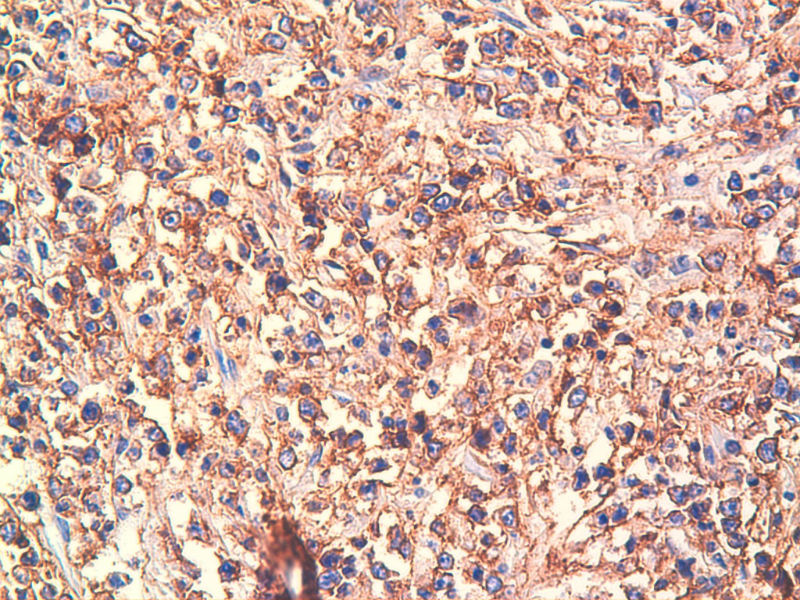

免疫组化染色:CA125(-),PLAP(-),NSE灶状阳性,Vimentin(+),a-inhibin(-),CK7(-),CK20(-),CD15(-),PSA(-),S100(-),MyoD1(-),CD38(-),CD56(-),HMB45(-),CK8(-),NF(-),CGA(-),syn(+),MPO散在(+)可能是炎细胞吧,LCA(+),CD133(+).

是的,syn(+),LCA(+), CD79a阳性, CD3阴性,NSE是局部胞核,胞浆着色,主要是胞浆着色;SYN也是局部,主要是胞核着色,胞浆很少。不对吗?我也迷糊。也许我看错了,不像那种典型的胞浆颗粒状着色。大家帮看一看。

今天又做了免疫组化,请大家帮看看。CD10(-),CD138(-),CDX2(-),CD3(-),CyclinD1(-),CD2(-),CD117(-),CD7(-),CD30(-),CD23(-);CD20强(+),BCL-2,Bcl-6,EMA,PAX-5,MUM-1,CD5,ALK,CD68都是散在阳性,大家帮确定一下是否阳性。B细胞淋巴瘤可以确定了,不知是哪种类型的?